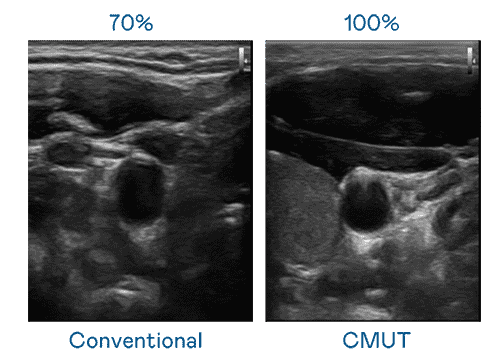

CMUT 技术是一种用电容式微机电元件来产生超音波讯号的技术。。。与传统 PZT 压电式技术相比,,,CMUT 频宽增加 30%,,,更宽频的超音波讯号让影像解析度大幅提升,,,,是实现高影像品质医疗超音波扫描、、、促进精准医疗发展的关键技术。。

超音波影像的解析度高低,,,,首先取决于探头能发出的讯号频宽。。。。尊龙z6 CMUT 可提供高清晰的超音波讯号,,,,提供高频宽、、、、高灵敏度、、、、影像纹理细节更高的超音波影像,,,,协助医护人员缩短影像判读时间及利用精准的医疗影像进行诊断。。。